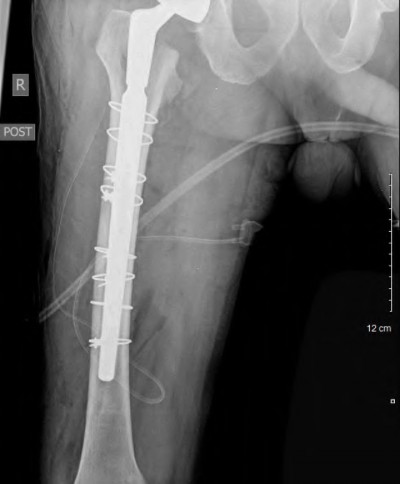

A 72-year-old male presents 2 years status post fixation of an impending pathologic right femur fracture due to metastatic renal cell carcinoma. He is minimally ambulatory due to pain. Despite radiation therapy, there has been progression of the lesion with extensive cortical bone loss, which is shown in Figure A. A proximal femoral replacement arthroplasty is performed without complications, and is demonstrated in Figure B. Which of the following is true regarding this patients post-operative course?

Deep prosthetic infection is the most common complication after hip arthroplasty performed for salvage of failed internal fixation after pathologic proximal femoral fracture secondary to malignancy.

Jacofsky et al reviewed the complications in 42 patients with a mean age of 63 who were treated with hip arthroplasty for salvage of failed treatment of a pathologic proximal femoral fracture. Multiple different constructs were used.

The most common complication was deep prosthetic infection, which occurred in nearly 10% of the patients studied. All infections occured in patients whom had previously received radiation. The mean Harris Hip score improved from 42 to 83 points post-operatively, and 41 of the 42 patients were ambulatory at follow-up. Implant survivorship free of revision for any reason at 5 years was 90%, and free of revision for aseptic failure or radiographic failure was 97%.

Figure A shows a lytic lesion of the proximal femur with an intramedullary implant. Figure B shows a proximal femoral replacement.